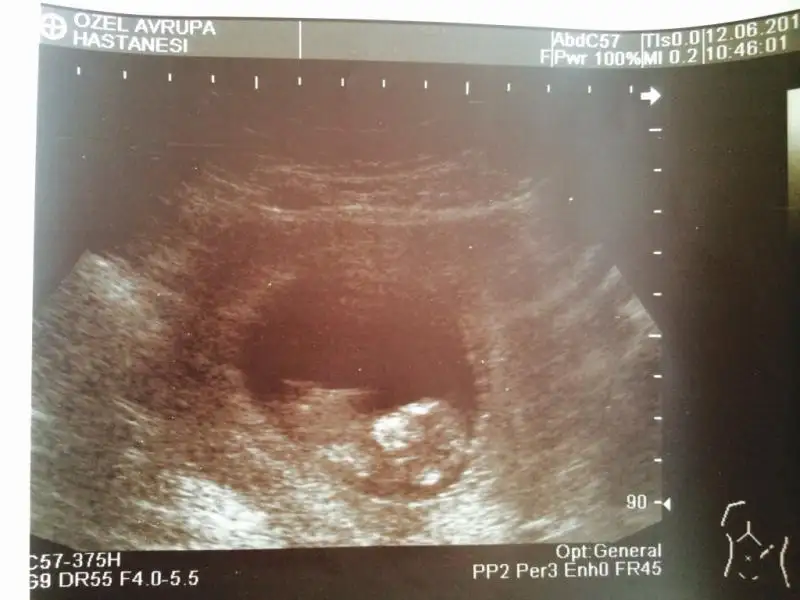

Merhaba kızlar..

Benim hamileliğim de bugün 12+5 oldu. ultrason fotografım 12+1 de çekildi. Doktorum birşey demedi, daha erken dedi. Siz ne diyorsunuz cinsiyet için?

bence kız canım

dr.um % 60 kıza benziyor dedi :) bakalım hayırlısı